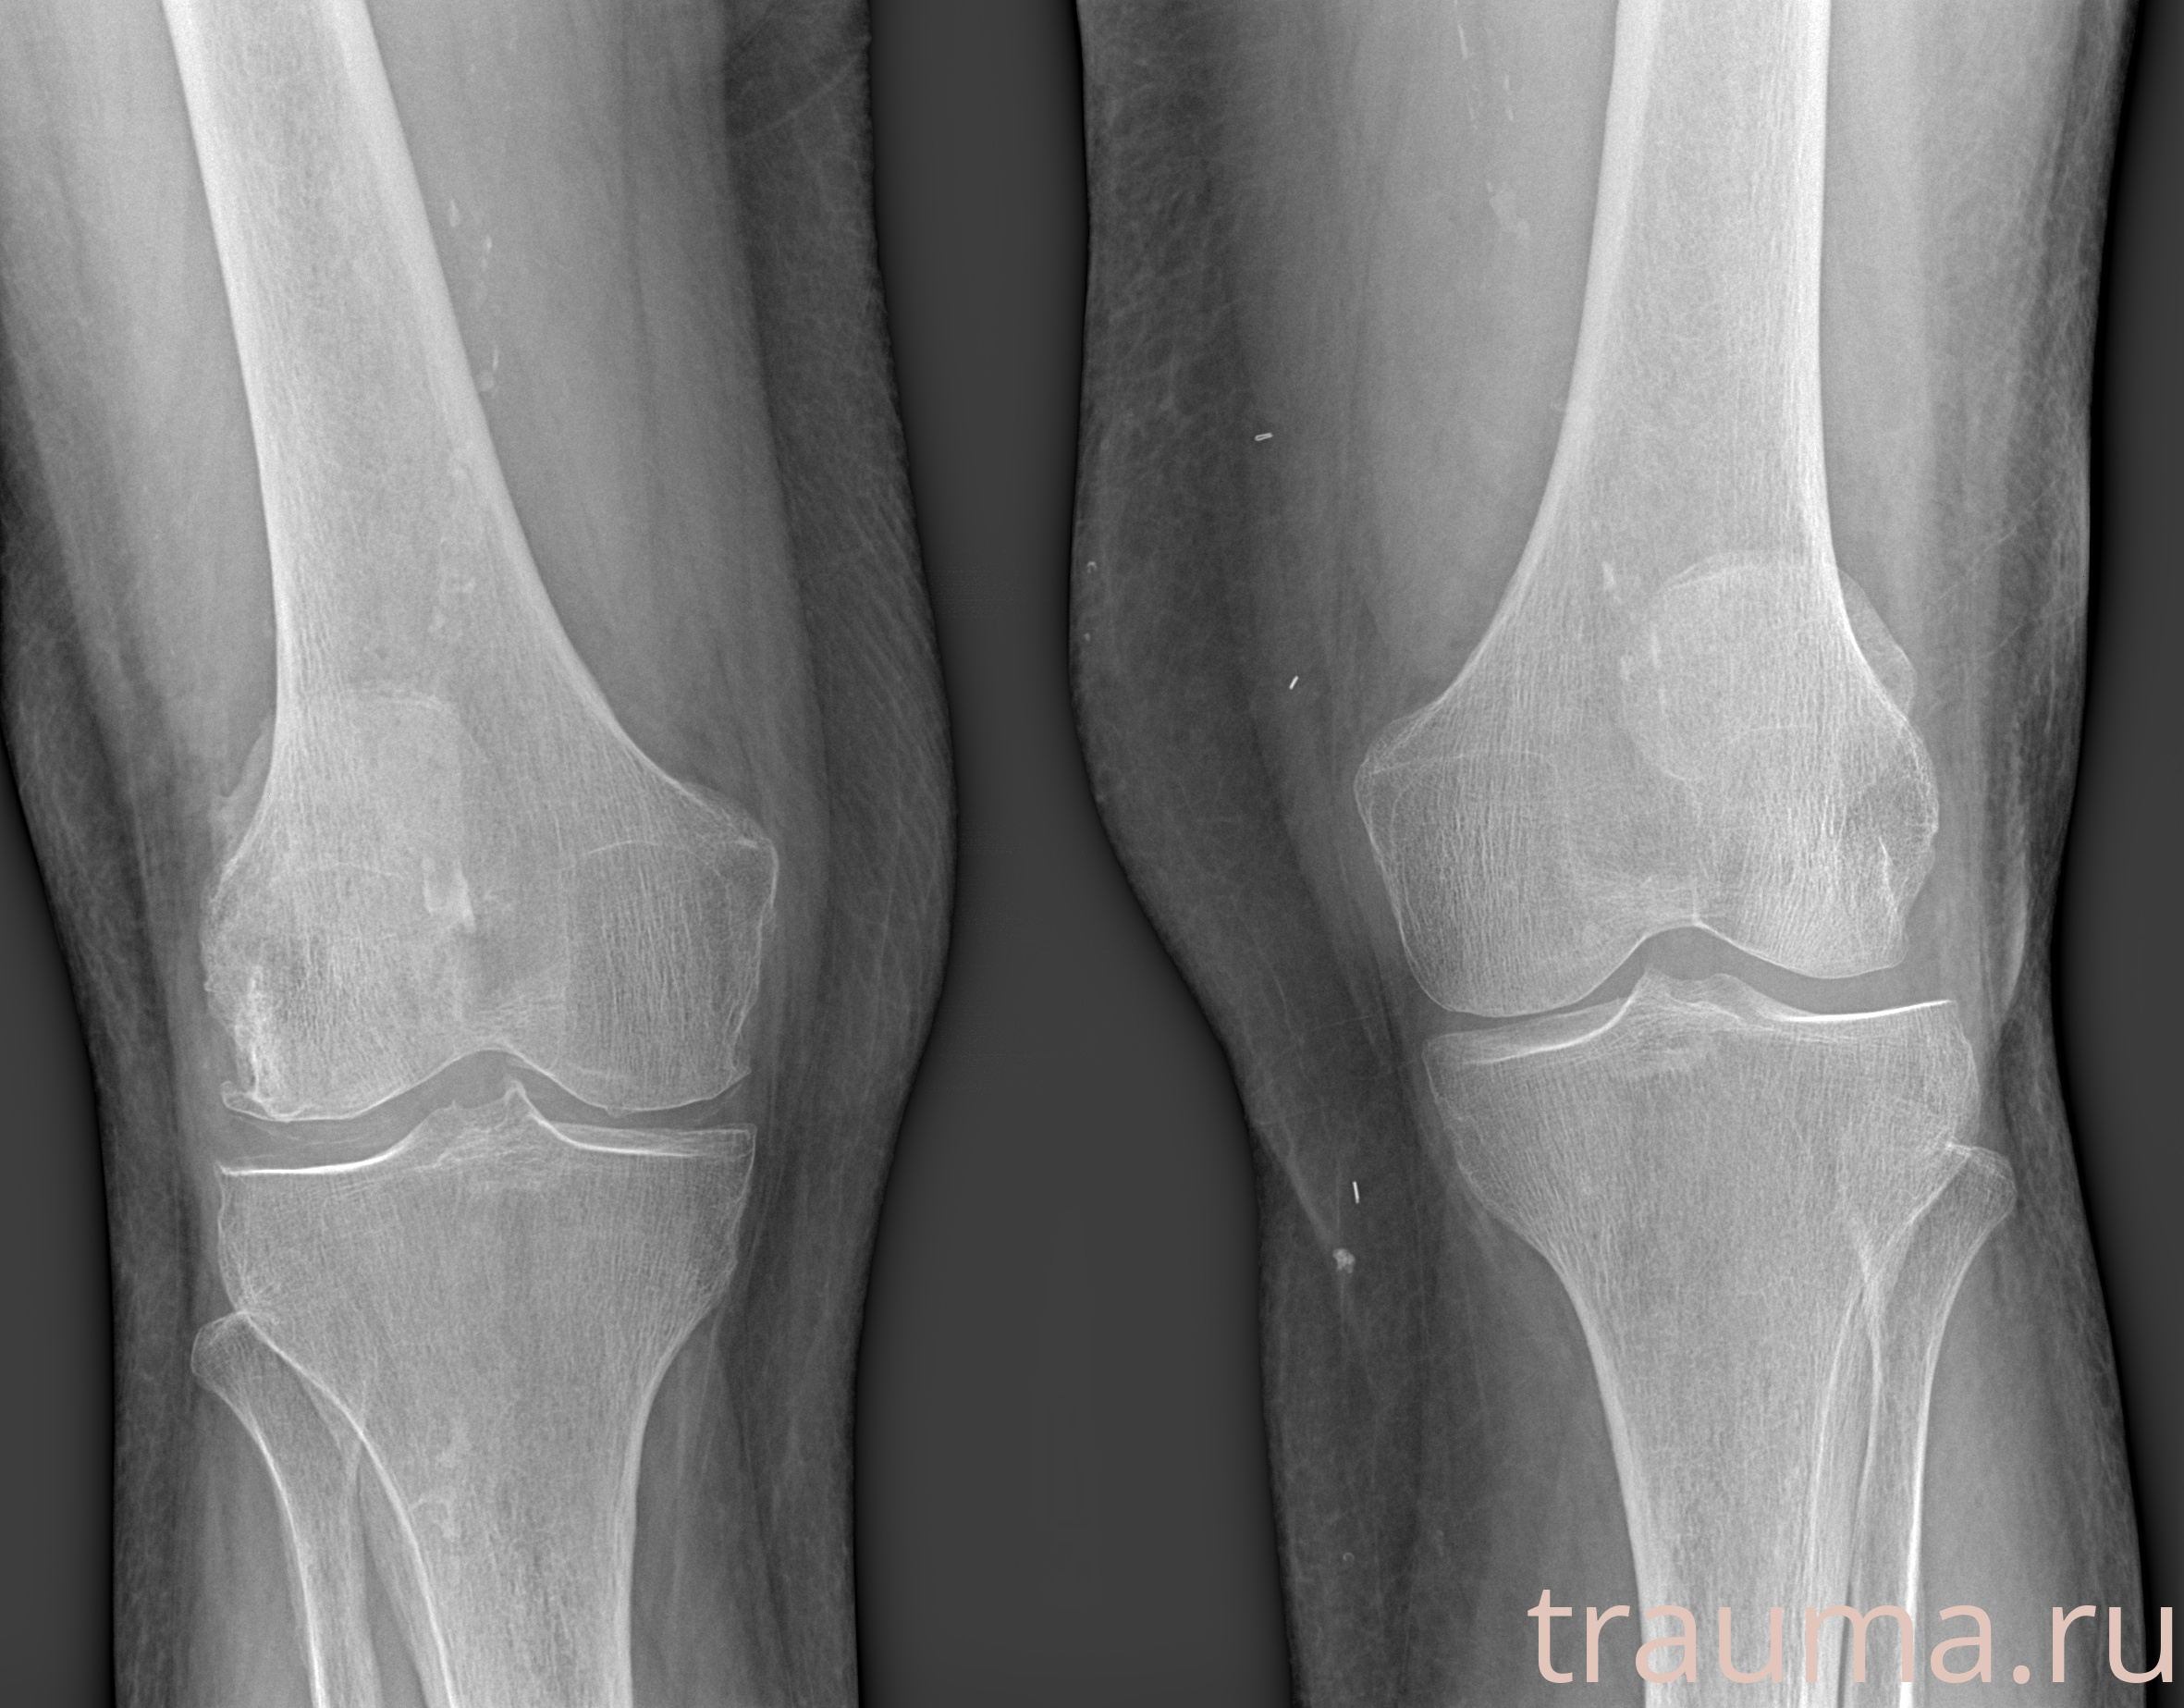

Рентгенограммы

Рентген на дому: по вашему адресу приезжает врач-рентгенолог, травматолог-ортопед с мобильным рентгеновским аппаратом, проводит диагностику травмы или заболевания, делает необходимые рентгенограммы, дает рекомендации по дальнейшему лечению. Получить качественные снимки в домашних условиях возможно благодаря уникальной методике, разработанной МосРентген Центром для института  Склифосовского